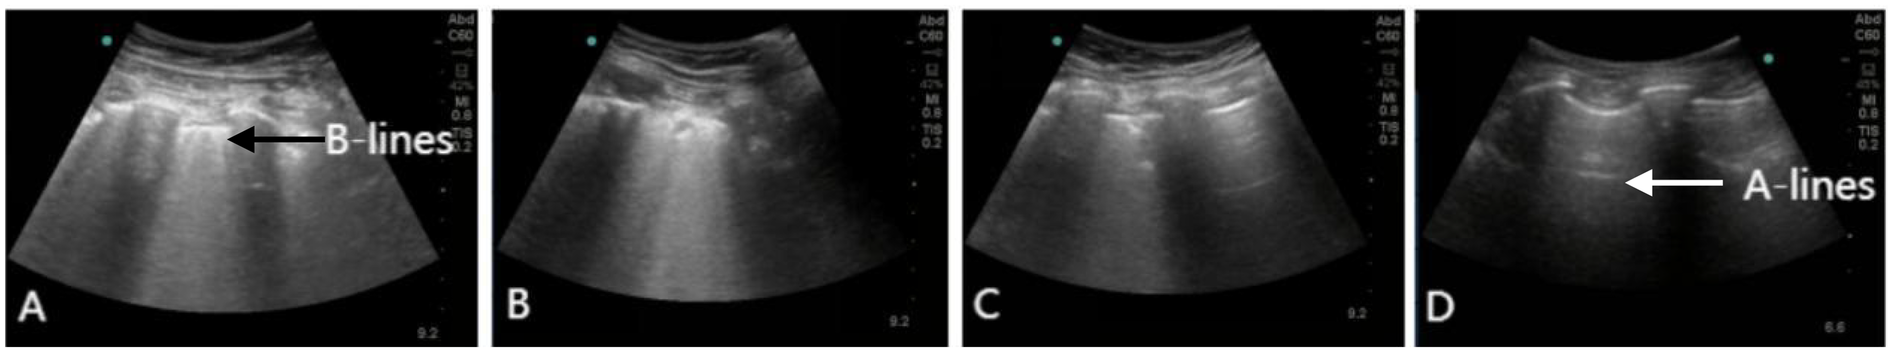

Figure 2

Lung ultrasound showing the resolution of RPE. (A) Lung ultrasound on day 1 demonstrating diffuse B-lines in the right lower lung. (B–D) Serial lung ultrasounds performed on day 3, 10, and 30 show progressive improvement. Real-time lung ultrasound identified A-lines (white arrow) and B-lines (black arrow).

During his ICU stay, serial assessments—including CXR (Figures 1A–D), lung ultrasounds (Figures 2A–D), computed tomography (CT; Figures 3B,C), and blood gas analyses—were obtained to monitor his condition. The chest CT revealed significant exudation in the right dorsal segment. Based on this finding, prone positioning ventilation (PPV) was initiated as an adjunct to the ongoing VV-ECMO therapy to treat the RPE (Figure 3D). By postoperative day 10, the patient's CXR demonstrated marked improvement and lung auscultation findings were unremarkable, enabling the discontinuation of VV-ECMO. The patient was successfully extubated on postoperative day 12 and was subsequently discharged on postoperative day 30 without sequelae. Transthoracic echocardiography prior to discharge demonstrated normal function of the prosthetic valve. Informed consent was obtained from the patient for the publication of his clinical details and images.

Although chest x-ray is convenient and provides a preliminary assessment of postoperative cardiopulmonary status, its accuracy in identifying imaging findings and underlying pathology is limited due to its anteroposterior projection and the constraints of the ICU environment. Lung ultrasound can serve as a powerful alternative to chest x-ray; compared to CT or x-ray, it allows more accurate classification of lung morphology. The anterior chest wall region is most accessible and useful for lung morphological classification (9). An increased number of B-lines on ultrasound is associated with elevated serum N-terminal pro-brain natriuretic peptide levels and an increased incidence of major adverse cardiovascular events (10). Due to its non-invasiveness, bedside availability, and widespread accessibility in various healthcare settings, lung ultrasound has an irreplaceable value in the diagnosis and management of RPE (11). It is also crucial for disease diagnosis, monitoring of disease progression, and evaluation of treatment efficacy. Bedside lung ultrasound facilitates rapid early recognition and management of RPE; real-time monitoring of cardiopulmonary function and early clinical intervention are also vital, enabling timely diagnosis and treatment.